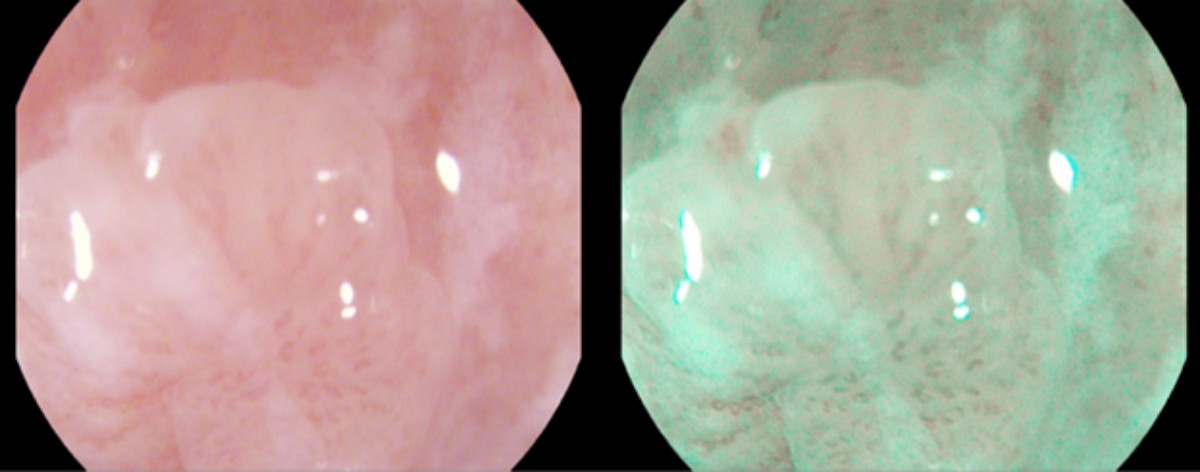

Рис. 1A. Шаг 1: выявление и макроскопическая оценка патологического очага в режиме двойного изображения в узком спектре на примере папилломы пищевода. Как видно из данного рисунка – визуализируется доброкачественное эпителиальное новообразование до 0,5 см с четкими контурами, однородной окраски.

Fig. 1A. Identification and macroscopic assessment of a pathological focus in the double image mode in a narrow spectrum by example esophageal papillomas. As can be seen from this figure, a benign epithelial neoplasm up to 0.5 cm with clear contours and uniform color is visualized.

Клинический пример

Пациентка С., 60 лет. Поступила на плановое обследование в связи с жалобами на дискомфорт в эпигастральной области, не связанный с приемом пищи. При проведении ЭГДС в ср/3 пищевода диагностировано эпителиальное новообразование на широком основании до 0,5 см, тип 0-1s по Парижской классификации. Результаты работы алгоритма представлены в виде визуализированных шагов по выявлению и макроскопической оценке патологического очага в режиме двойного изображения в узком спектре (рис. 1 (A-G). Проведена детальная оценка границ, микроструктуры, ангиоархитектоники, определен предположительный тип морфологической структуры патологического очага, осуществлен выбор тактики эндоскопического хирургического лечения в режиме узкого спектра с оптическим увеличением в 136 раз (рис. 1В).

Рис. 1B. Шаг 2. Детальная оценка границ, микроструктуры, ангиоархитектоники, предположительный тип морфологической структуры патологического очага, выбор тактики эндоскопического хирургического лечения в режиме узкого спектра с оптическим увеличением в 136 раз. Микроструктура слизистой оболочки эпителиального новообразования недеформирована, ангиоархитектоника четко прослеживается, регулярная, сосудистый рисунок расширен, признаков неопластической перестройки не обнаружено.

Fig. 1B. A detailed assessment of the boundaries, microstructure, angioarchitectonics, the presumed type of morphological structure of the pathological focus, the choice of tactics of endoscopic surgical treatment in a narrow spectrum mode with an optical magnification of 136 times. The microstructure of the mucous membrane of the epithelial neoplasm is not deformed, the angioarchitectonics is clearly traced, regular, the vascular pattern is expanded, there are no signs of neoplastic restructuring.

Микроструктура слизистой оболочки эпителиального новообразования не деформирована, ангиоархитектоника четко прослеживается, регулярная, сосудистый рисунок расширен, признаков неопластической перестройки не обнаружено. Принято решение о проведении холодной полипэктомии биопсийными щипцами в режиме механической резекции в амбулаторных условиях (рис. 1С).